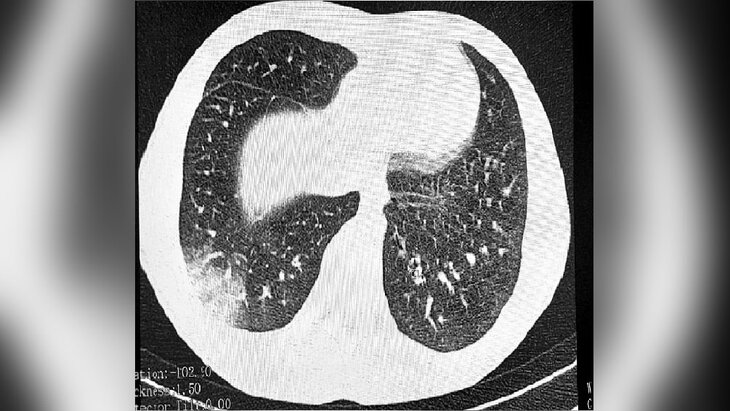

Фото: телеграм-канал "Роспотребнадзор Томск"

Новую болезнь EVALI, которая возникает из-за вейпов, обнаружили у подростка в Томске. Об этом сообщается в телеграм-канале регионального управления Роспотребнадзора.

Врачи выявляют заболевание во время прослушивания легких, которые издают звук, напоминающий треск лопающегося попкорна. Из-за этого болезнь называют также и "попкорновой". Она проявляется в виде воспаления, образования рубцов в легких и сужения бронхиол.